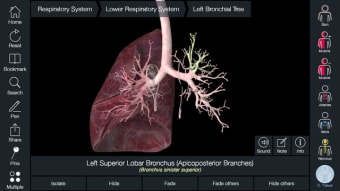

หากคุณต้องการค้นหากระดูก อวัยวะที่เฉพาะเจาะจง หรือกล้ามเนื้อ คุณเพียงแค่ค้นหาตามส่วนต่างๆ ของร่างกาย แล้ว Essential Anatomy จะเน้นตรงจุดที่พวกเขาอยู่ด้วย คำอธิบายที่เป็นประโยชน์ของแต่ละส่วน สิ่งเดียวที่ขาดคือภาพเคลื่อนไหวของอวัยวะและกล้ามเนื้อในการทำงาน

Essential Anatomy ใช้งานง่ายมาก ฟังก์ชันการค้นหาคือสิ่งที่คุณต้องการมากที่สุดหากคุณกำลังเรียนอยู่ แม้ว่าคุณจะสนุกสนานไปกับการสำรวจและหมุนร่างกายก็ตาม คุณสามารถแยกชั้นของกล้ามเนื้อและเนื้อเยื่อออกเพื่อเผยให้เห็นสิ่งที่อยู่ภายใต้ ซึ่งจะช่วยให้คุณมีความคิดที่ดีขึ้นมากเกี่ยวกับการทำงานของร่างกาย มากกว่าที่จะอ่านมันในหนังสือ